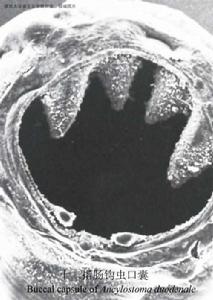

| 概述: | 學名:美洲板口線蟲(Necator americanus stiles,1992),簡稱美洲鉤蟲。隸屬勾口科(Ancylostomatidae)線蟲。鉤蟲的成蟲寄生在人體的小腸,致人體長期慢性失血,引起鉤蟲病(hookworm disease),患者可出現貧血及與貧血相關的症狀,感染重者,能明顯影響勞動力,甚至威脅生命,目前,全世界鉤蟲感染的人數超過13億人,其中有臨床症狀的越600萬人左右。中國的平均感染率為14.89%,感染人數為2億左右。 成蟲體長約1cm左右,半透明,肉紅色,死後呈灰白色。蟲體前端較細,頂端有一發達的口囊,由堅韌的角質構成。因蟲體前端向背面仰曲,口囊的上緣為腹面、下緣為背面。十二指腸鉤蟲的口囊呈扁卵圓形,其腹側緣有鉤齒2對,外齒一般較內齒略大,背側中央有一半圓形深凹,兩側微呈突起。美洲鉤蟲口囊呈橢圓形。其腹側緣有板齒1對,背側緣則有1個呈圓錐狀的尖齒(圖16-9,16-10)。鉤蟲的咽管長度約為體長的1/6,其後端略膨大,咽管壁肌肉發達。腸管壁薄,由單層上皮細胞構成,內壁有微細絨毛,利於氧及營養物質的吸收和擴散。 |